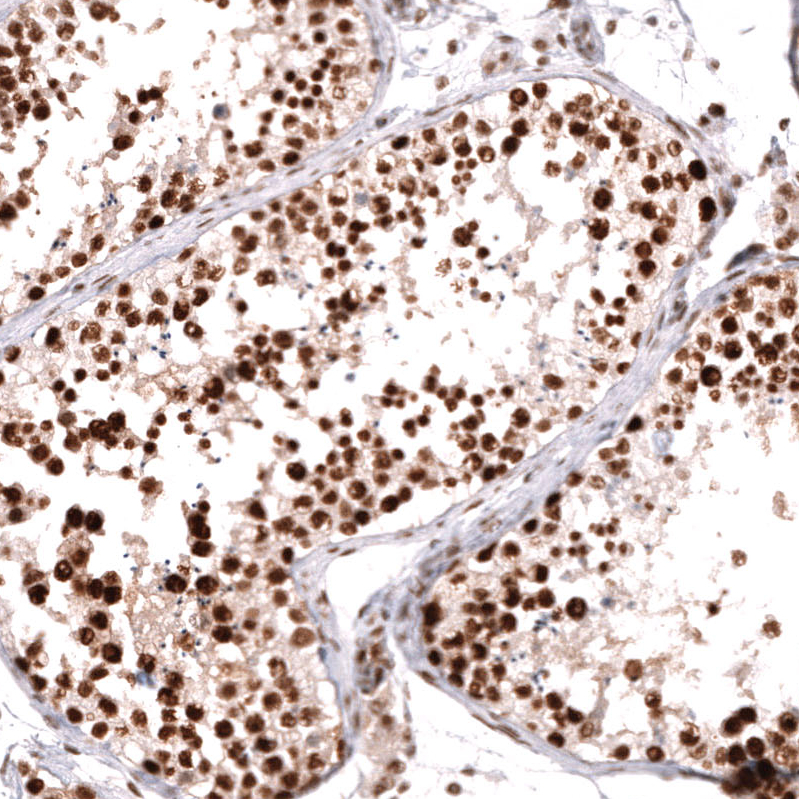

Immunohistochemistry analysis in human lymph node and liver tissues using AMAb91892 antibody. Corresponding MSH2 RNA-seq data are presented for the same tissues.